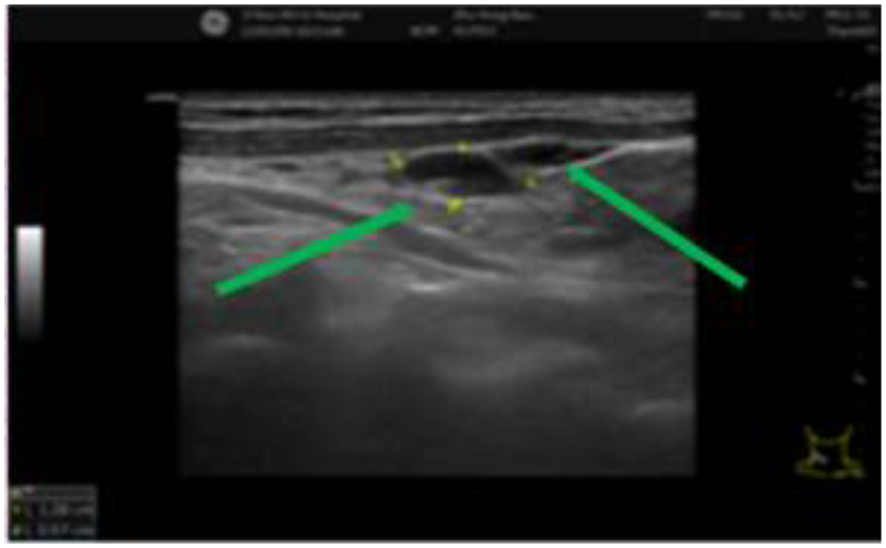

Figure 3

Multiple cervical lymph nodes of varying sizes can be seen and are indicated by green arrows. The lymph nodes exhibit clear structures and well-defined boundaries.